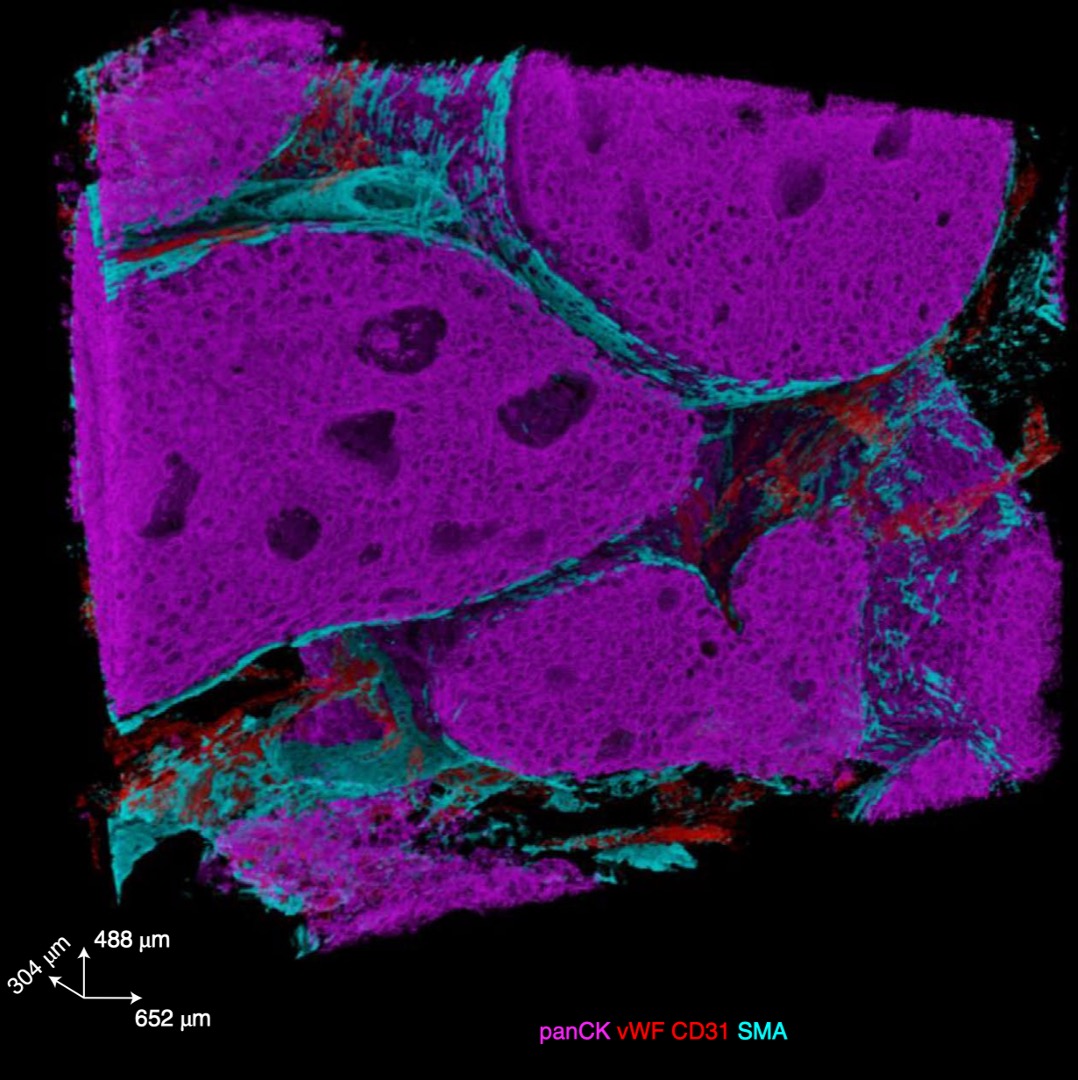

Three-dimensional imaging mass cytometry for highly multiplexed molecular and cellular mapping of tissues and the tumor microenvironmentLaura Kuett, Raúl Catena, Alaz Özcan, Alex Plüss, IMAXT Consortium, Peter Schraml, Holger Moch, Natalie Souza, and Bernd BodenmillerNature Cancer, 2022

Three-dimensional imaging mass cytometry for highly multiplexed molecular and cellular mapping of tissues and the tumor microenvironmentLaura Kuett, Raúl Catena, Alaz Özcan, Alex Plüss, IMAXT Consortium, Peter Schraml, Holger Moch, Natalie Souza, and Bernd BodenmillerNature Cancer, 2022A holistic understanding of tissue and organ structure and function requires the detection of molecular constituents in their original three-dimensional (3D) context. Imaging mass cytometry (IMC) enables simultaneous detection of up to 40 antigens and transcripts using metal-tagged antibodies but has so far been restricted to two-dimensional imaging. Here we report the development of 3D IMC for multiplexed 3D tissue analysis at single-cell resolution and demonstrate the utility of the technology by analysis of human breast cancer samples. The resulting 3D models reveal cellular and microenvironmental heterogeneity and cell-level tissue organization not detectable in two dimensions. 3D IMC will prove powerful in the study of phenomena occurring in 3D space such as tumor cell invasion and is expected to provide invaluable insights into cellular microenvironments and tissue architecture.

@article{kuett2022three, dimensions = {true}, title = {Three-dimensional imaging mass cytometry for highly multiplexed molecular and cellular mapping of tissues and the tumor microenvironment}, author = {Kuett, Laura and Catena, Ra{\'u}l and {\"O}zcan, Alaz and Pl{\"u}ss, Alex and Consortium, IMAXT and Schraml, Peter and Moch, Holger and de Souza, Natalie and Bodenmiller, Bernd}, journal = {Nature Cancer}, volume = {3}, number = {1}, pages = {122--133}, year = {2022}, publisher = {Nature Publishing Group US New York}, doi = {10.1038/s43018-021-00301-w}, } -